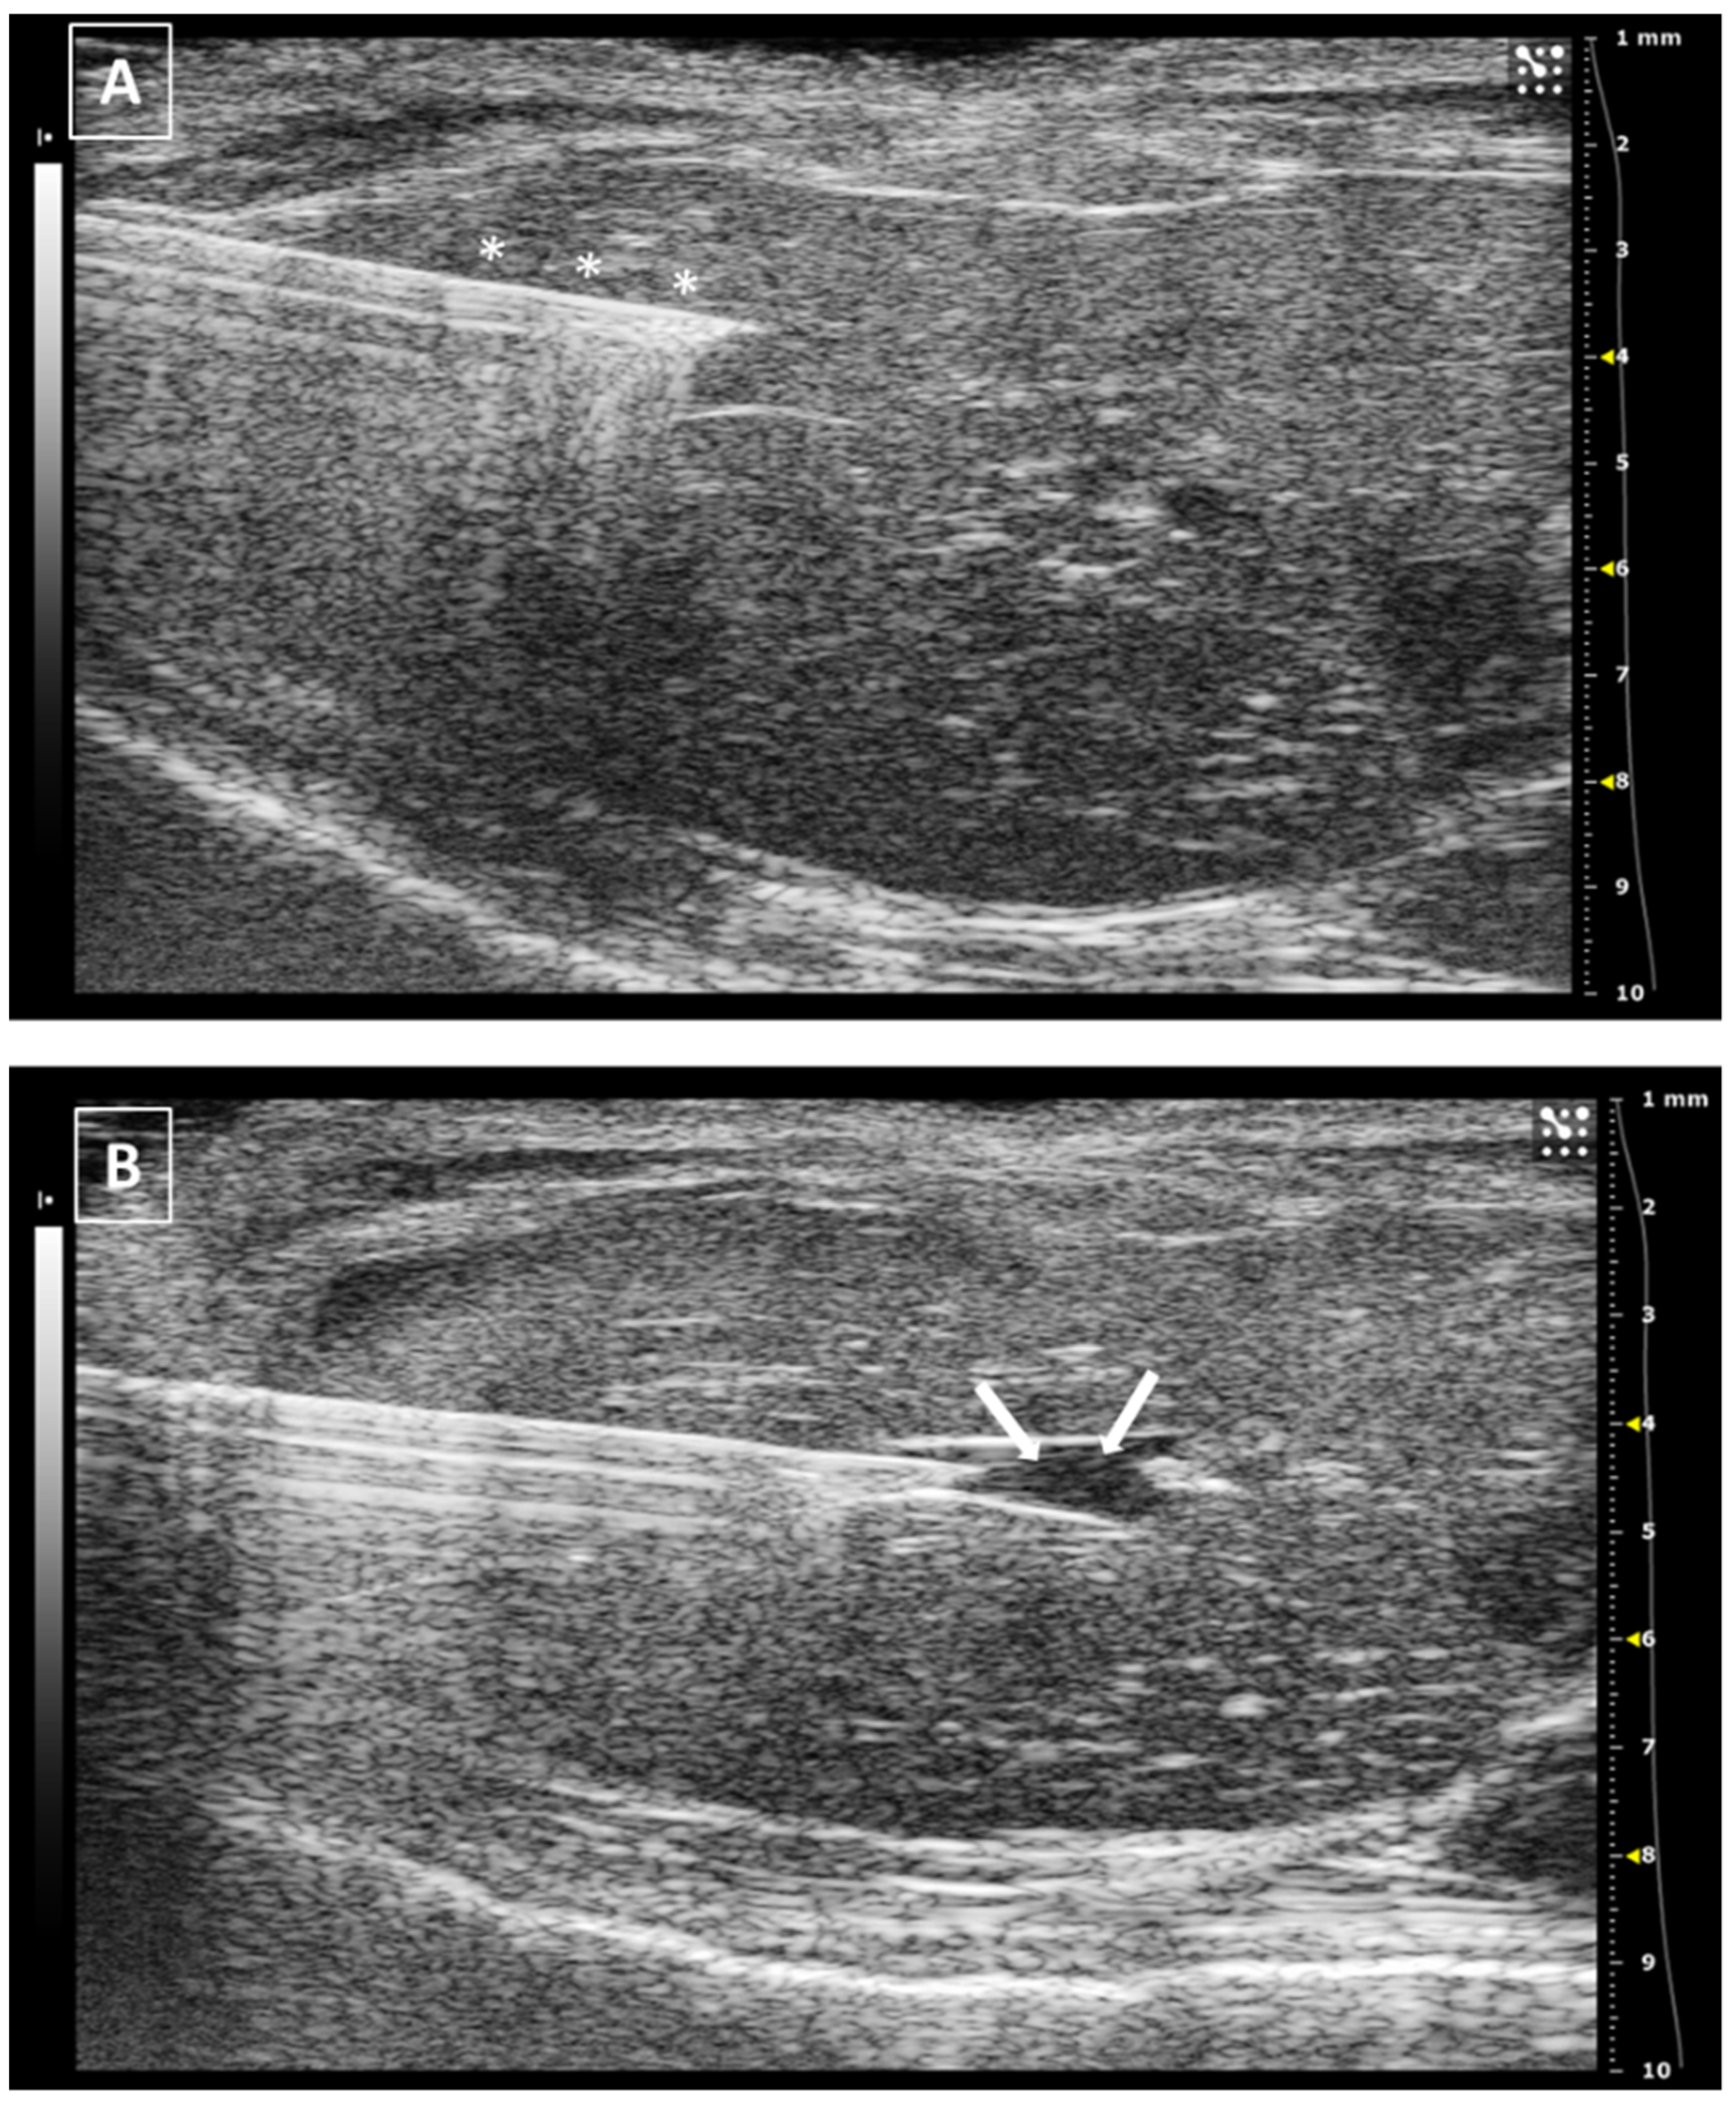

For intrathyroidal injections, a ventral approach is required, positioning the mouse in ventral recumbence and removing the hair of the neck and cranial part of the thorax. The front limbs are fixed with tape in a caudal position, close to the ribs. Intubation of the animal is not required and anesthesia can be supported with a facial mask. After the application of ultrasonographic gel, the scan starts locating the trachea in transversal view at the hyoid bone level. It is recognized due to the acoustic shadow produced by the intratracheal air. Moving the probe caudal, the salivary glands will appear as two superficial, bilateral, hypoechoic, and big structures. At this level, we will need to slightly increase the pressure of the probe against the neck for improving the visualization of deeper structures. Going caudal, a muscular band will appear in the middle line, ventral to the trachea, followed by two bilateral structures, the sternohyoideus and sternothyroideus muscles. The carotid arteries and jugular veins will be visible at this point. The first ones are smaller but have a pulse. We can check the blood flow direction using the Color Doppler mode of the ultrasound system. In a standardized position of the probe (left side of the probe placed over the right side of the animal), the arterial flow should be colored in red and the jugular veins should appear in blue (Figure 2).

The thyroid glands will be located at this level, dorsal and slightly medial to the neck vessels. In a standardized exam, they will appear under the vessels. They are composed of soft tissue, so the echogenicity will be lower than the salivary glands but higher than the vessels. Their shape is irregularly ellipsoidal. The best approach for the puncture is lateral, placing the needle under the ultrasound probe. If the needle is placed correctly in the injection support, we will see it coming from the lateral of the screen (Figure 2). The hardest part of the injection is piercing the skin and for this purpose, we can use forceps for immobilizing the skin. The maximum volume we can inject is low due to the organ size, so more than 10 to 20 microliters in each gland is not recommended [18,19,20].

Figure 2. Thyroid gland injection. (A) Doppler mode of the medium level of the neck, where the jugular veins are colored in blue while the carotid arteries in red. Salivary glands marked with a black asterisks and neck muscles with a white arrow. (B) B mode during the thyroid injection. The needle is marked with white asterisks, and the thyroid gland is surrounded by a dashed line. Trachea cartilage is signaled with white arrows. Images acquired with 40 MHz frequency in B mode and 32 MHz in Doppler mode.